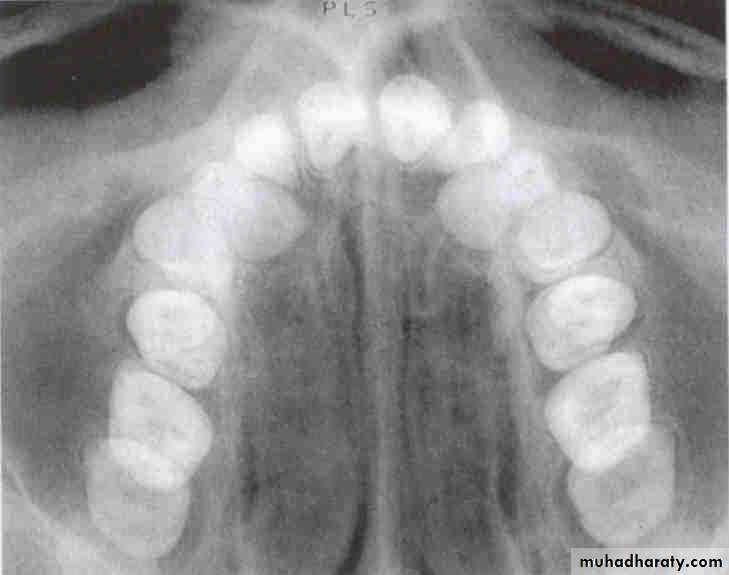

Is the maxillary second premolar (arrows) displaced to the buccal or the lingual?

premolar filmmolar film

premolar bitewing

4The tube head moves distally from the premolar film to the molar film. The second premolar also moves distally, overlapping the first molar more in the molar film. In moving from the premolar periapical to the bitewing, the tube head moves down and the premolar also moves down. The displacement is to the lingual.